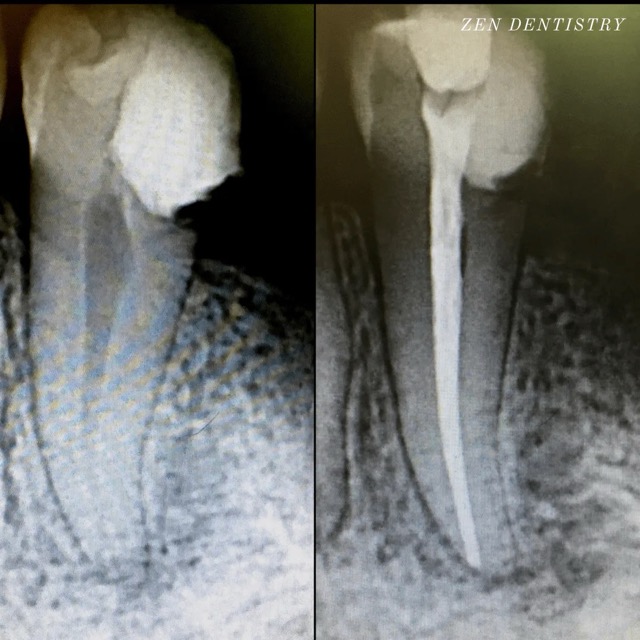

Patient presented to the office with a concern that the tooth has been causing severe constant pain that would become worse at night time and biting. A detailed clinical exams including endodontic screening and x rays let to the diagnosis of irreversible pulpitis (inflammation of the nerve) due to existing filling that was very close to the pulp and symptomatic apical periodontitis (inflamed ligaments).

The tooth was taken out of the bite and pain medication was prescribed to see if the pain could be resolved without having to do a RCT. However tooth responded in the same manner after a week. So it was decided to do a RCT. Root Canal treatment was performed that included removing the caries, dead nerve tissue and disinfecting the canals with proper medication to achieve a 3D hermetic seal of the canals to save the tooth.